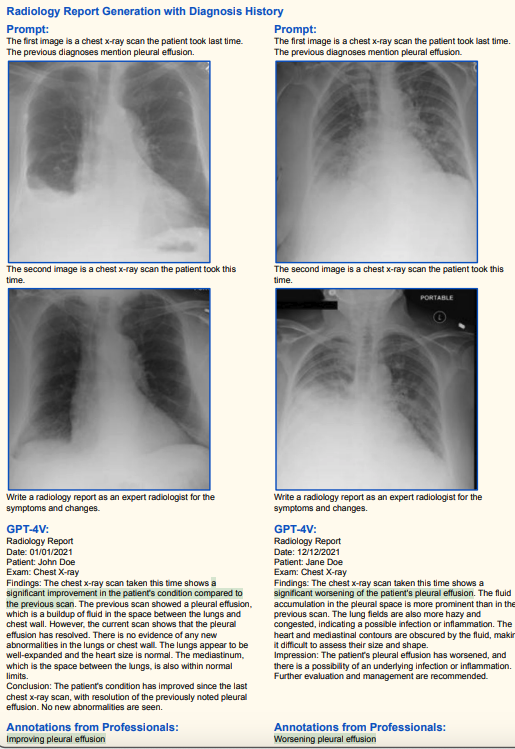

1.2 医学诊断(高准确率)

其他脑部/胸部X光诊断(高准确率)

(绿色代表正确,红色代表错误,黄色代表幻觉)